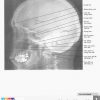

Atlas Giải Phẫu Đầu Cổ (Netter) | Bài giảng CĐHA

* Tác giả: Frank H. Netter v6 – 2016

Giải Phẫu X-Quang Sọ Mặt | Bài giảng CĐHA